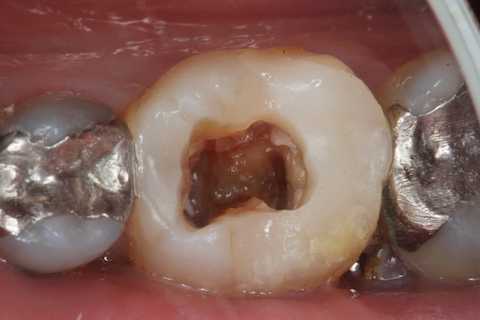

残根上のCR8 2025.10.28

伝説の根管治療法4(Per+GA、3MIX+α-TCP) 2025.10.27